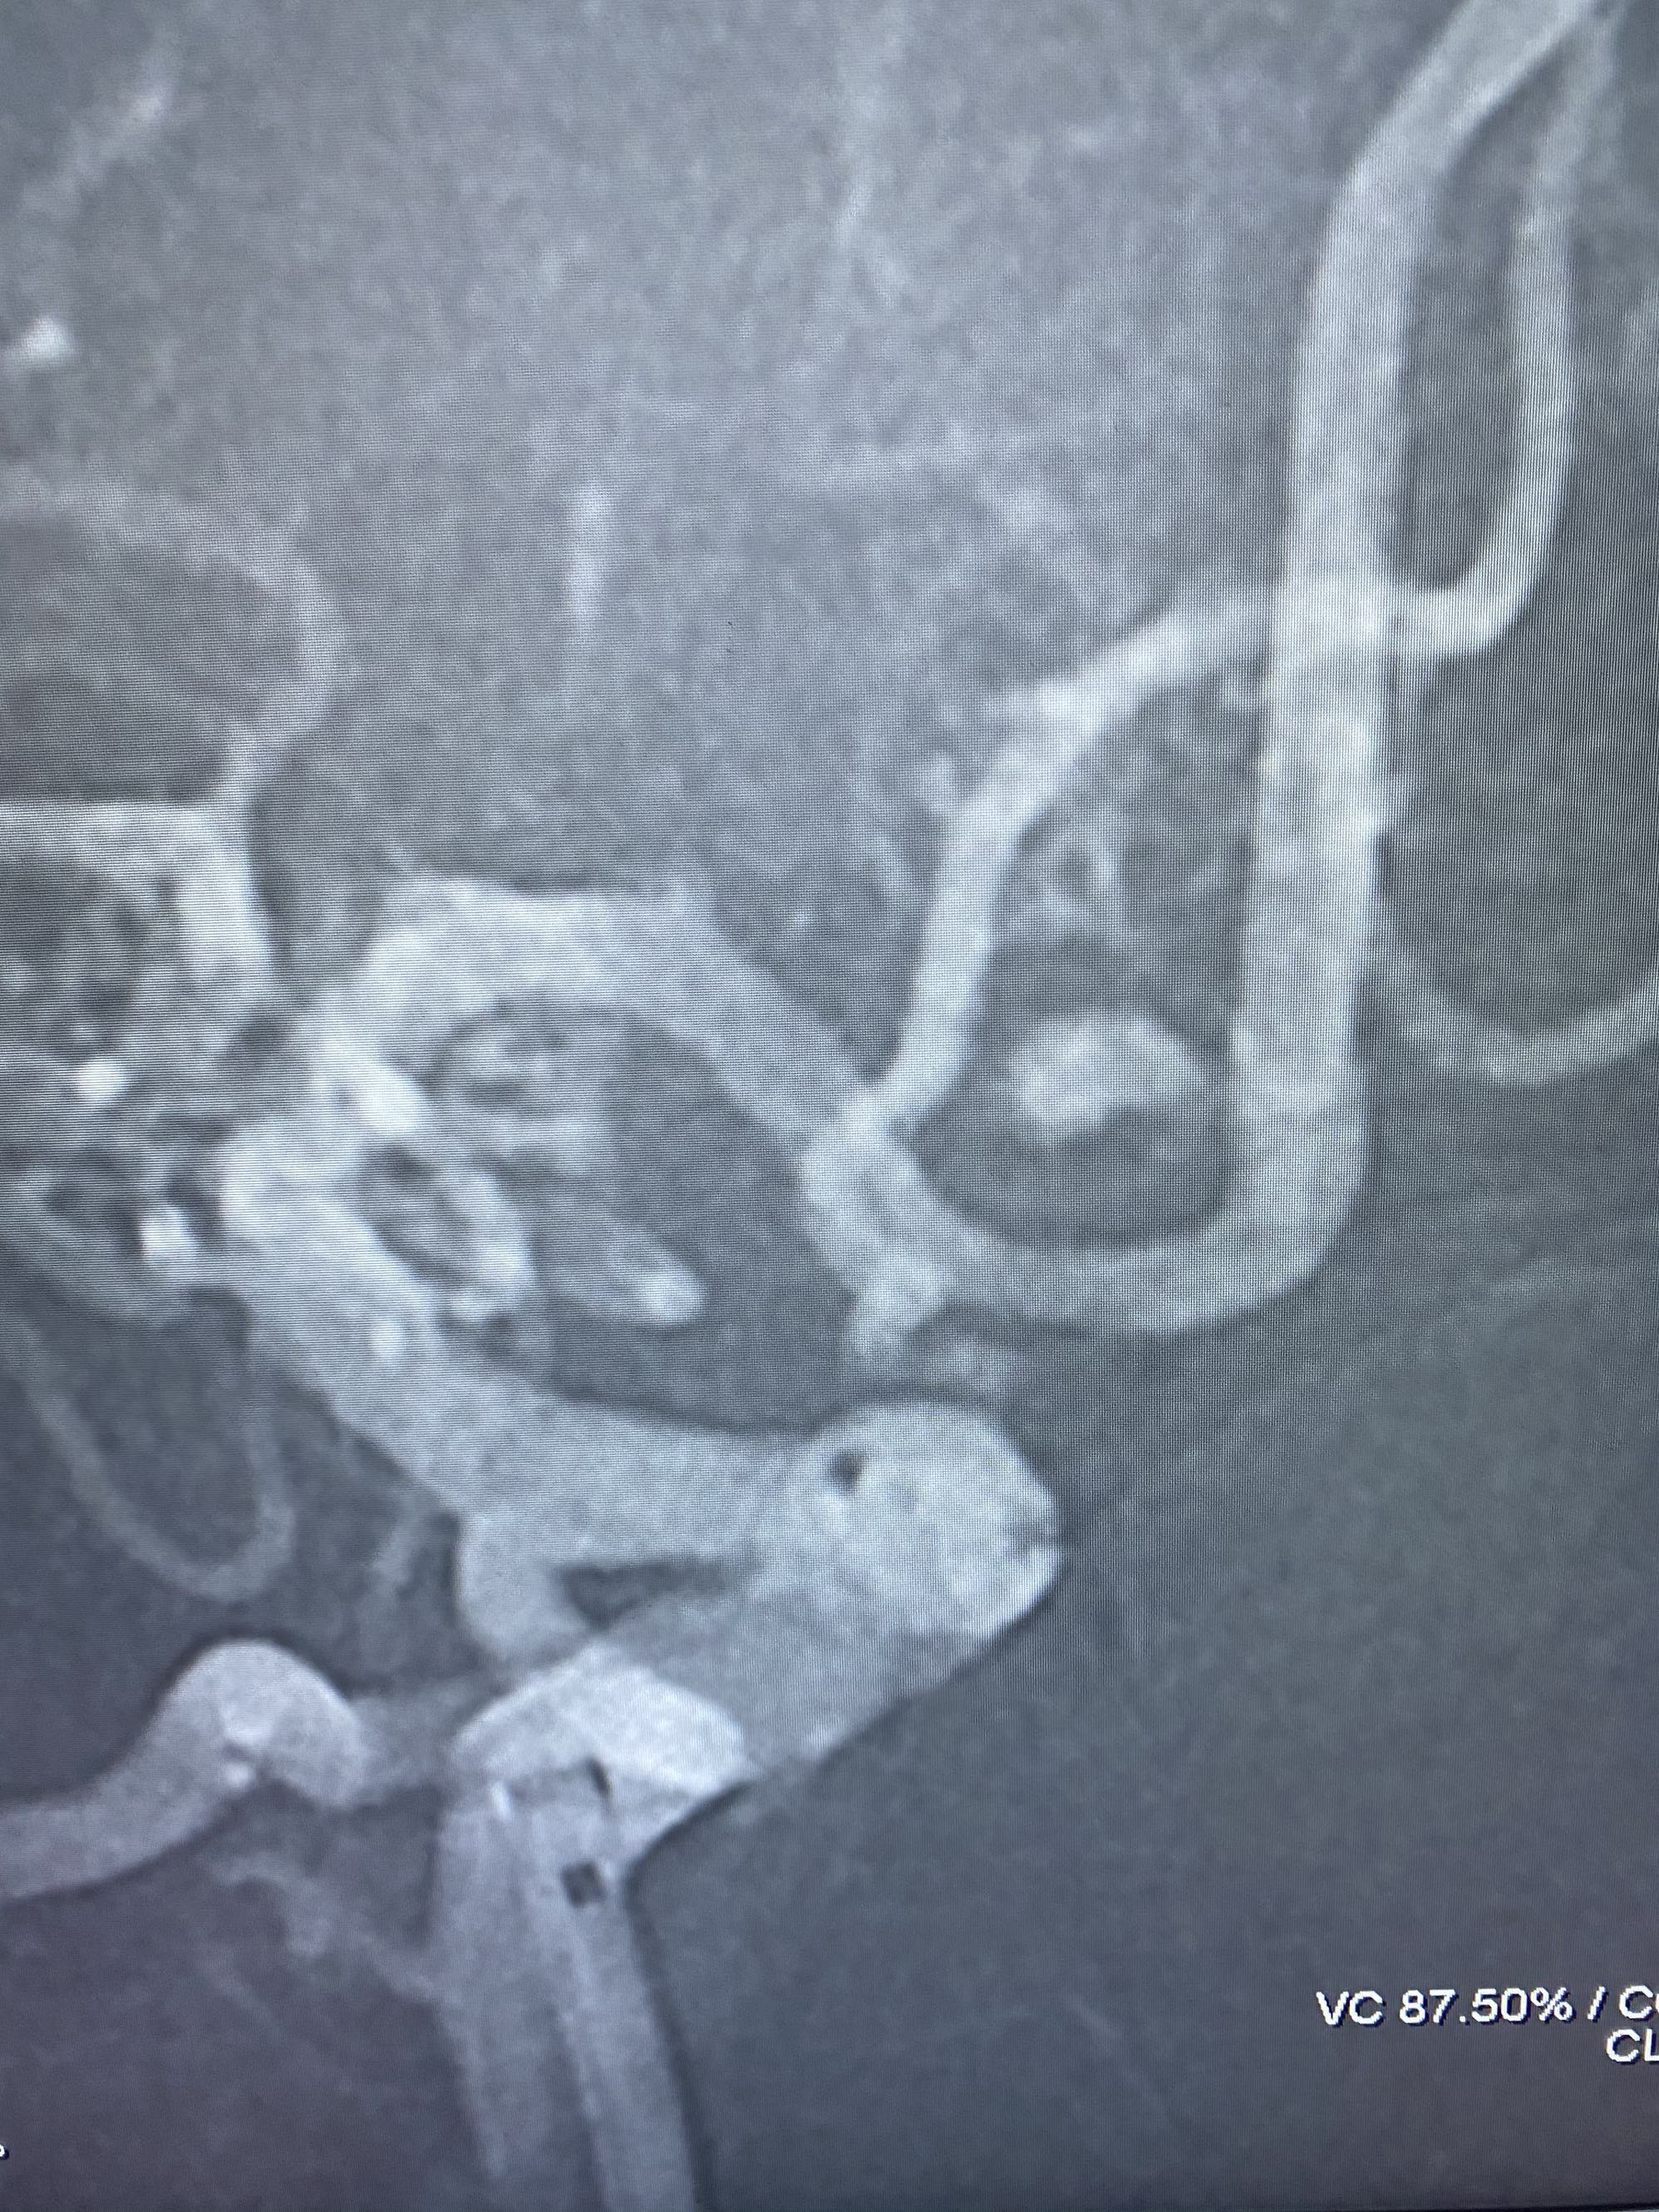

MLS,M79Y,sah,双侧MCA烟雾病,Heubner返动脉瘤,前交通段开窗,细支发出Heubner返动脉,瘤颈细长,瘤颈口比微导管细,弹簧圈2mmx3cm“隔山打牛”填塞治愈,Heubner返动脉保留。